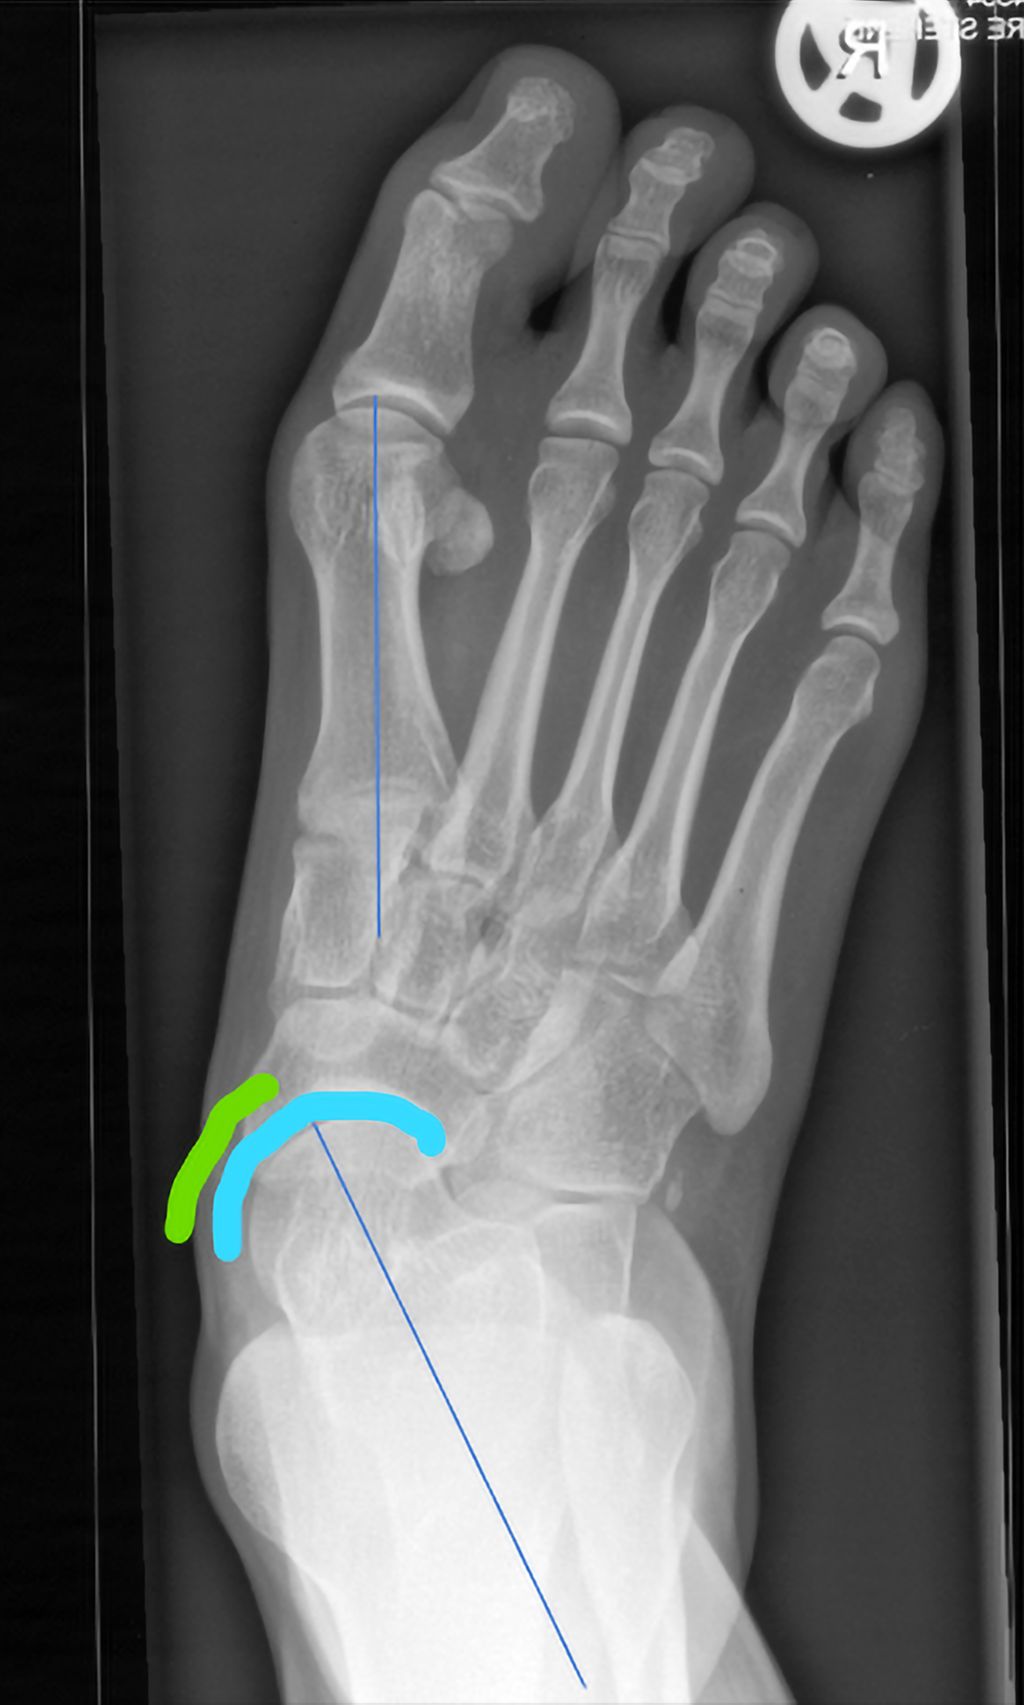

Abb. 1: Präoperativ: blaue Linie = Talus-MT1-Winkel; gebogene Linien: „talar head uncoverage“

Die Röntgenaufnahmen des Fußes und des oberen Sprunggelenks im dorsoplantaren (d.p.) und seitlichen Strahlengang erfolgen am belasteten Bein, um die Fehlstellung in ihrem vollen Ausmaß zu erfassen. Zusätzlich wird für die nativradiologische Abklärung eine Rückfußaufnahme nach Saltzman durchgeführt, in der die Valgisierung des Fersenbeines gegenüber der Tibiaachse dargestellt wird.

Die d.p. Aufnahme zeigt das Ausmaß der Abduktion des Vorfußes, die talonaviculare Überdeckung („talar head uncoverage“, Abb. 1).3 Degenerative Veränderungen der einzelnen Gelenke werden beurteilt.